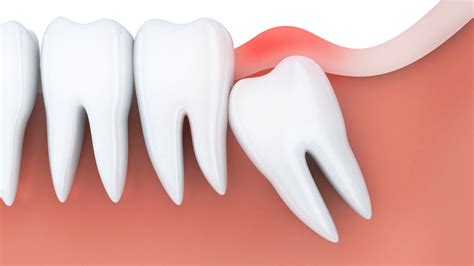

The primary reason most people experience trouble with wisdom teeth coming in is an evolutionary mismatch. Human jaws have become smaller over time, yet our third molars continue to develop as if we still needed them for heavy-duty chewing of tough, uncooked food. When there isn't enough space, these teeth become impacted.

Impacted wisdom teeth can grow at various angles: toward the adjacent molar, toward the back of the mouth, or staying trapped completely within the jawbone. Below is a breakdown of how different types of impaction affect your oral health:

Impaction Type Description Risk Factor

Soft Tissue Impaction The tooth has broken through the gum but not fully. High risk of infection (pericoronitis).

Partial Bony Impaction The tooth is partially encased in the jawbone. Difficult to clean; high risk of cavities.

Full Bony Impaction The tooth is entirely enclosed in the jawbone. Potential for cysts or damage to adjacent teeth.